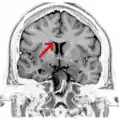

Sagittal section of a brain, front part to the left. The corpus callosum can be seen in the center, in light gray

The corpus callosum (Latin for "tough body"), also callosal commissure, is a wide, thick nerve tract, consisting of a flat bundle of commissural fibers, beneath the cerebral cortex in the brain. The corpus callosum is only found in placental mammals.[1] It spans part of the longitudinal fissure, connecting the left and right cerebral hemispheres, enabling communication between them. It is the largest white matter structure in the human brain, about 10 cm (3.9 in) in length and consisting of 200300 million axonal projections.[2][3]

The corpus callosum forms the floor of the longitudinal fissure that separates the two cerebral hemispheres. Part of the corpus callosum forms the roof of the lateral ventricles.[5]